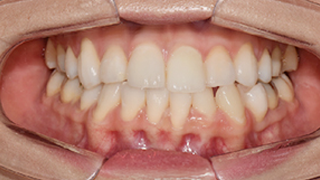

Orthodontic

Before & After Photos

View more